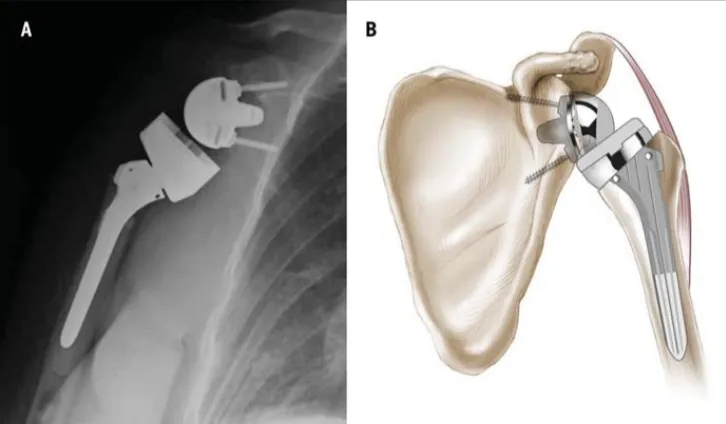

Anterior posterior radiograph of a right shoulder (A) and an illustration of a left shoulder (B) after

reverse total shoulder arthroplasty.

Photo adapted from Boudreau et al., 2007